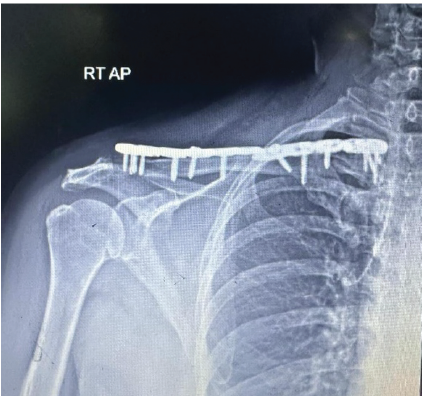

Figure 5: Fracture reduced and fixed with 3 and 4 hole lateral clavicular plate over medial and lateral, respectively.

To avoid stress raisers, plates were fixed at different planes. Early mobilization was initiated post-operatively. Arm abduction was restricted to <90°. For 12 weeks, weight-bearing activities were avoided. Weekly follow-up was advised for the initial 6 weeks, followed by 3 weeks of follow-up till 3 months, subsequently at 6 months interval [fig-6/7]. The 6-week post-operative X-ray showed signs of fracture healing and a maintained anatomical reduction. The 1-year follow -up X-ray showed a united fracture. Outcome was assessed using the Disability of the Arm, Shoulder, and Hand score.

Figure 6: Post-operative X-ray, showing reduced bipolar clavicle fracture.

Figure 7: Post-operative X-ray, showing reduced bipolar clavicle fracture.